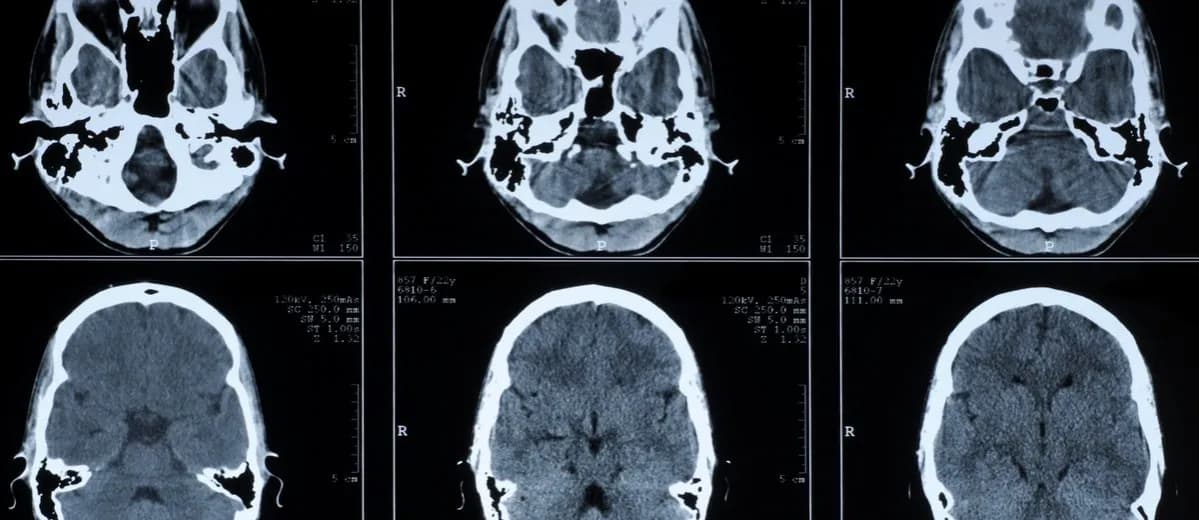

Bildgebende Verfahren: Visualisierung für bessere Entscheidungen

Bildgebende Verfahren sind ein weiterer wichtiger Bestandteil der medizinischen Diagnostik. Sie ermöglichen eine visuelle Darstellung der inneren Strukturen des Körpers, was für die Diagnose von Krankheiten unerlässlich ist. Zu den gängigen bildgebenden Verfahren gehören Röntgenuntersuchungen, Computertomografie (CT) und Magnetresonanztomografie (MRT). Diese Techniken helfen Ärzten, anatomische Veränderungen zu erkennen und Krankheitsprozesse zu beurteilen.

Die Anwendung von bildgebenden Verfahren ist entscheidend, um präzise Diagnosen zu stellen und die geeigneten Behandlungsmöglichkeiten zu wählen. Sie sind besonders hilfreich bei der Diagnose von Tumoren, Verletzungen und anderen Erkrankungen, die durch strukturelle Veränderungen im Körper gekennzeichnet sind. Durch die Kombination von bildgebenden Verfahren mit anderen diagnostischen Methoden können Ärzte ein umfassendes Bild des Gesundheitszustands ihrer Patienten erhalten.